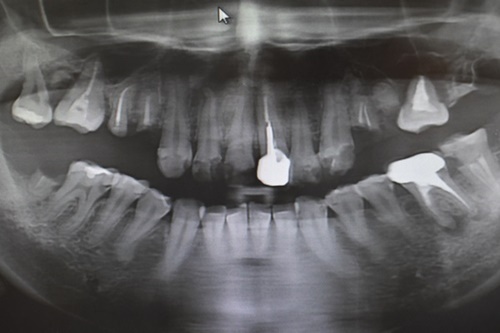

簡單先跟林醫師描述自己口腔缺牙的忐忑史跟狀況後,林醫師便是替我進行了洗牙跟牙齒現況的檢查,果不其然這段期間的過往蛀牙有部分再度復發,林醫師也仔細跟我講解即使治療好蛀牙,缺牙也屬口腔不健康的一種現象,有人會因為缺牙位置不明顯,而將其忽略增加蛀牙發生率。

檢查過後,由於牙周病的關係牙槽骨質密度較低,所以須採用人工種牙來做治療,透過補骨粉之後這樣種植體才會更加穩固,而非近年來相當盛行的傷口較小、復原速度也較快的微創種牙,當然,如果是真的可以做到改變自己的口腔狀況且減少後顧之憂,基本上已經下了要進行口腔狀況調整的決心,自然就不會輕易退卻,再說,有如此專業、仔細林義城醫師,跟制度完全的醫療團隊,加上新穎且俱全的診間設備,到底還有什麼好讓人擔憂的呢?